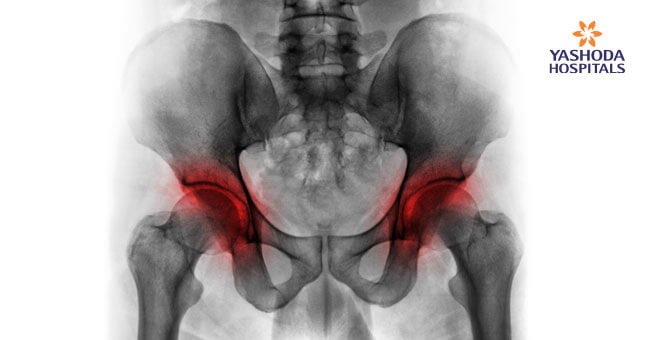

A lack of blood supply to the tissue within the bone leads to its death called Avascular necrosis or Osteonecrosis. It can sometimes lead to tiny breaks within the structure of the bone and eventually its collapse. The hip is the most commonly affected area with osteonecrosis. Other than the hip, commonly affected areas are the knee, shoulder, hand and foot.

The early stages of avascular necrosis may not be associated with any symptoms. However, the affected joint may begin to hurt as the condition progresses and the person puts on weight in the affected area. The primary symptom of avascular necrosis is pain which develops gradually and can be mild or severe. Sometimes the pain may persist even on lying down. The pain is located at the centre of the groin or radiates to the area of the thigh or buttock. In certain persons, (4 to 5 out of 10) avascular necrosis may be bilateral, i.e., it develops on both hip joints.

- X-rays: Determine the bone changes in the later stages of avascular necrosis.